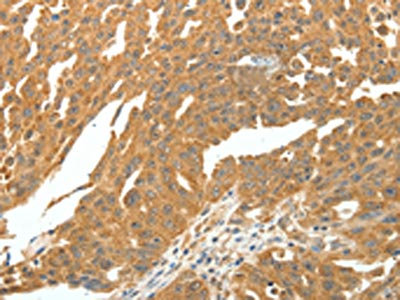

The image on the left is immunohistochemistry of paraffin-embedded Human breast cancer tissue using CSB-PA371951(SKP1 Antibody) at dilution 1/30, on the right is treated with fusion protein. (Original magnification: ×200)

The image on the left is immunohistochemistry of paraffin-embedded Human ovarian cancer tissue using CSB-PA371951(SKP1 Antibody) at dilution 1/30, on the right is treated with fusion protein. (Original magnification: ×200)